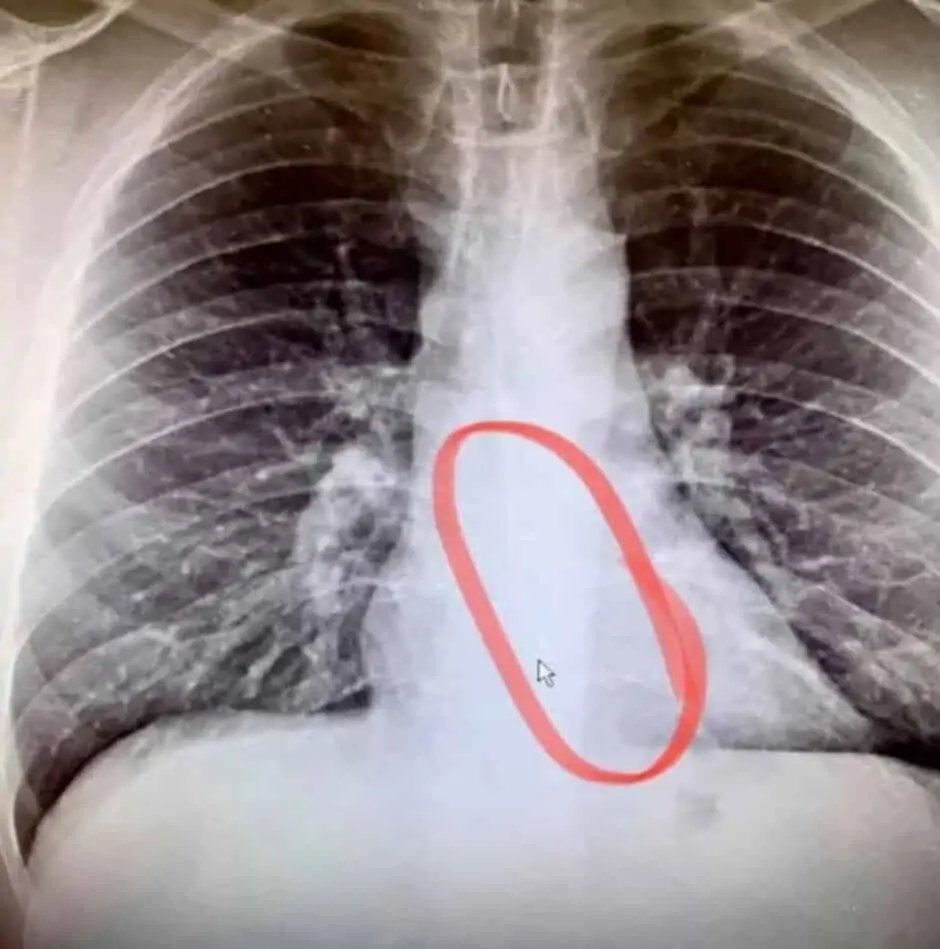

Entretanto ele foi para o hospital. Aí e depois do Raio X percebeu-se que tinha um AirPod preso no esófago. Uma endoscopia de emergência removeu o auricular. A única coisa que aconteceu foi um pequeno desconforto. Bradford admitiu que teve sorte e afirmou que “O médico revelou que é extremamente incomum que um bloqueio não seja doloroso ou extremamente desconfortável. Nunca me ocorreu que dormir com auriculares pudesse ser um risco à segurança. Quanto ao AirPod que ele acidentalmente engoliu continua a funcionar com o áudio perfeito. No entanto, o microfone tem algumas falhas.

Abaixo está uma foto com o auricular removido tirada do Facebook da pessoa que teve de passar por este problema. Continua intacto.